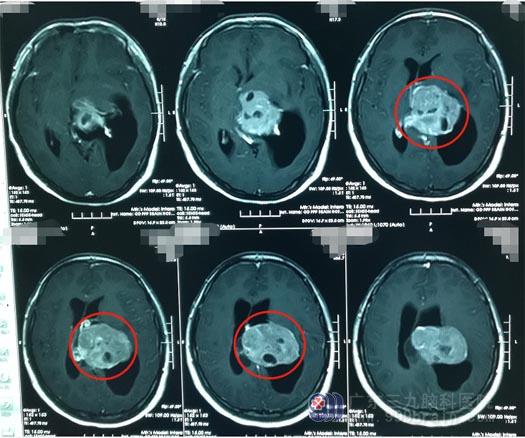

▲影像检查

入院完善相关检查,结合患者的临床症状,我院副院长、神经外五科主任鲁明初步诊断为脑膜瘤。但从影像检查结果及临床表现来看,患者的病程较长、肿瘤体积大、位置深,这些都为手术带来了较大的难度,术中稍有不慎将可能导致昏迷,甚至死亡。

经过反复研究讨论,最终神经外五科团队为患者制定了详细的手术计划,于6月底为患者实施左侧侧脑室巨大占位切除术。术中,鲁明切除一个直径5cm的肿瘤。